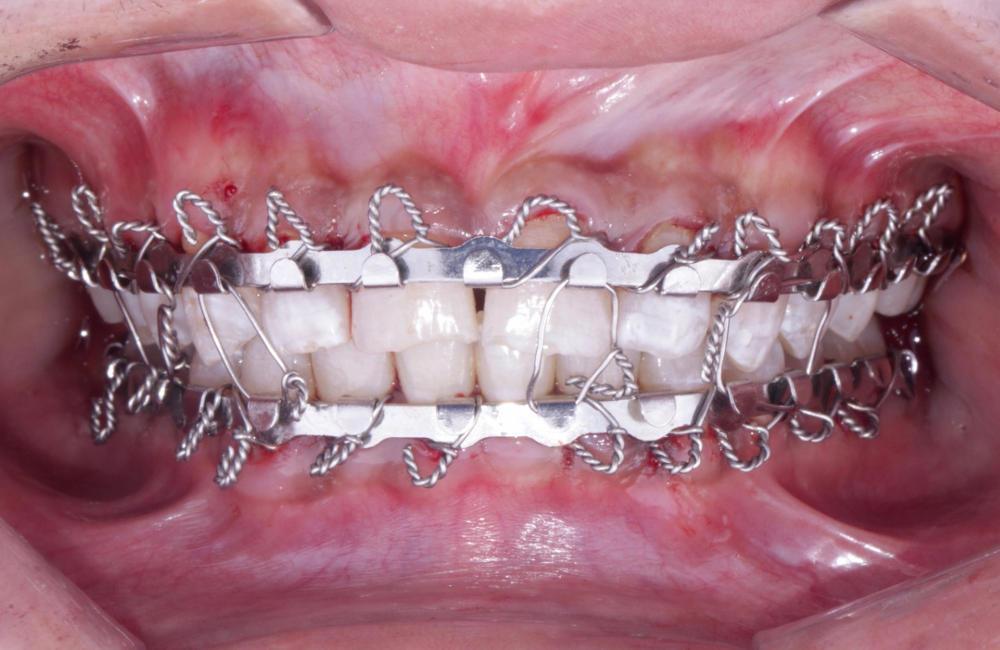

Corrección de fractura mandibular

TRATAMIENTO

REALIZADO

• Cirugía Oral

antes Corrección de fractura mandibular despues Corrección de fractura mandibular

DESPUés